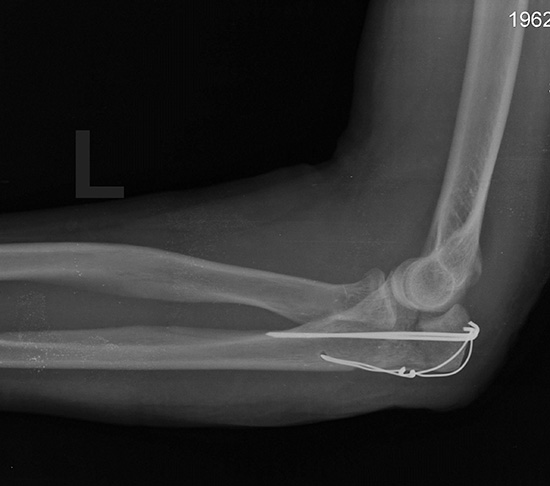

Ко мне обратился Клиент, который пояснил, что он ехал в транспортном средстве в качестве пассажира, которое попало в дорожно-транспортное происшествие. В результате этого, Клиент получил телесное повреждение, а именно тяжёлый перелом правой руки, причинивший вред здоровью средней тяжести. Виновником в совершении указанного ДТП, был водитель другого транспортного средства, а именно молодой парень, который не изъявил желания добровольно компенсировать моральный вред Клиенту.